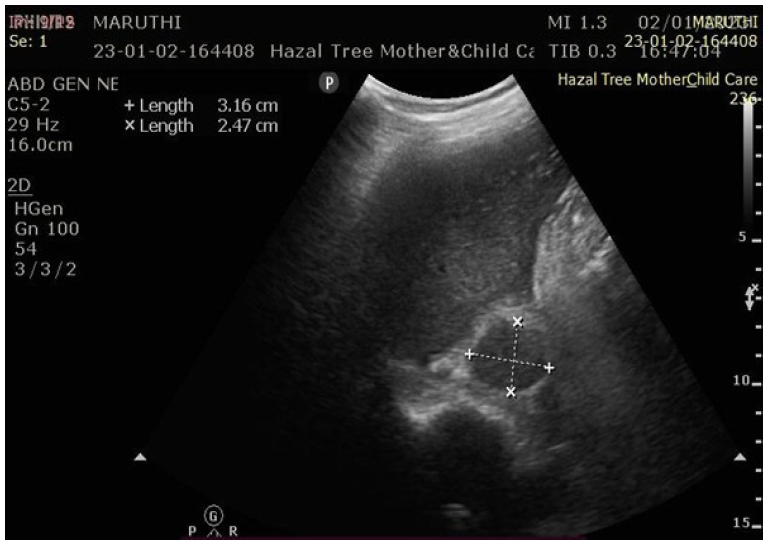

Ultrasonography (USG) evaluation

Ultrasonography was performed to assess adrenal haematomas with respect to site, size, mass effect, and appearance, categorized as early-stage or late-stage haematoma (Figure 1 and 2).